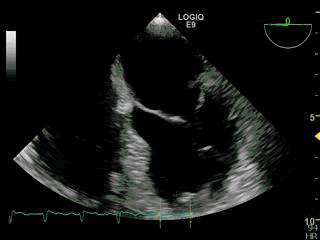

但今天我们来说说最常见射血分数,它是患者做心脏超声很常见的一项数据,它如果低于40%,那么心脏性猝死的风险将会大大增加。

射血分数(EF值)指心脏每次搏动射出的血液量占心脏舒张末期容积量的百分比,临床上常用左心室射血分数来表示,正常值为50-70%[1],这就意味着心脏每收缩一次可以把心脏50%-70%的血液泵出心脏之外。反应心脏收缩功能的指标,一般通过心脏彩超来测量,它与机体多种心血管疾病预后相关。

心源性猝死即心脏原因导致的患者突然死亡,它的主要征兆之一是左心室收缩功能下降,而左室射血分数(LVEF)是最常用、最重要的左室收缩功能指标。通过心脏超声能够较准确的测定出左心室的射血分数(LVEF),对判断心功能状态、指导用药及预后有重要的意义。